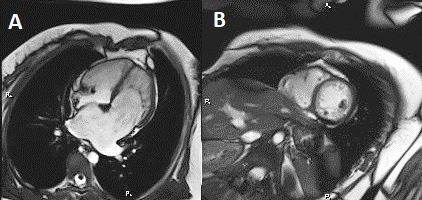

При МРТ сердца с контрастным усилением у Веры К. фиброзных изменений в миокарде очагового или диффузного характера не выявлено. Имело место выраженная дилатация ЛП (длина 57 мм, ширина 68 мм), умеренное снижение систолической функции ЛЖ (до 50%) и ПЖ (до 37%), признаки рестрикции, повышенная трабекулярность ЛЖ и некомпактность миокарда обоих желудочков (толщина некомпактного слоя в ЛЖ составляла 30 мм, в ПЖ – 16 мм) (рис. 3). У Любы Г. отмечалась выраженная дилатация ЛП (длина 71 мм, ширина 73 мм), систолическая функция ЛЖ в норме (68%), повышенная трабекулярность миокарда, наиболее выраженная в апикальных отделах, а также признаки некомпактности миокарда обоих желудочков (соотношение некомпактной части к компактной составляет 3:1 и более). Фиброзных изменений в миокарде очагового или диффузного характера не определялось (рис. 4).

Рис. 3. Магнитно-резонансная томография сердца Веры К. от 08.12.2017 г. Проекция по длинной оси (А) и по короткой оси на уровне папиллярных мышц (В). Имеет место выраженная дилатация ЛП, признаки рестрикции, повышенная трабекулярность ЛЖ и некомпактность миокарда обоих желудочков (толщина некомпактного слоя в ЛЖ составляла 30 мм, в ПЖ – 16 мм).